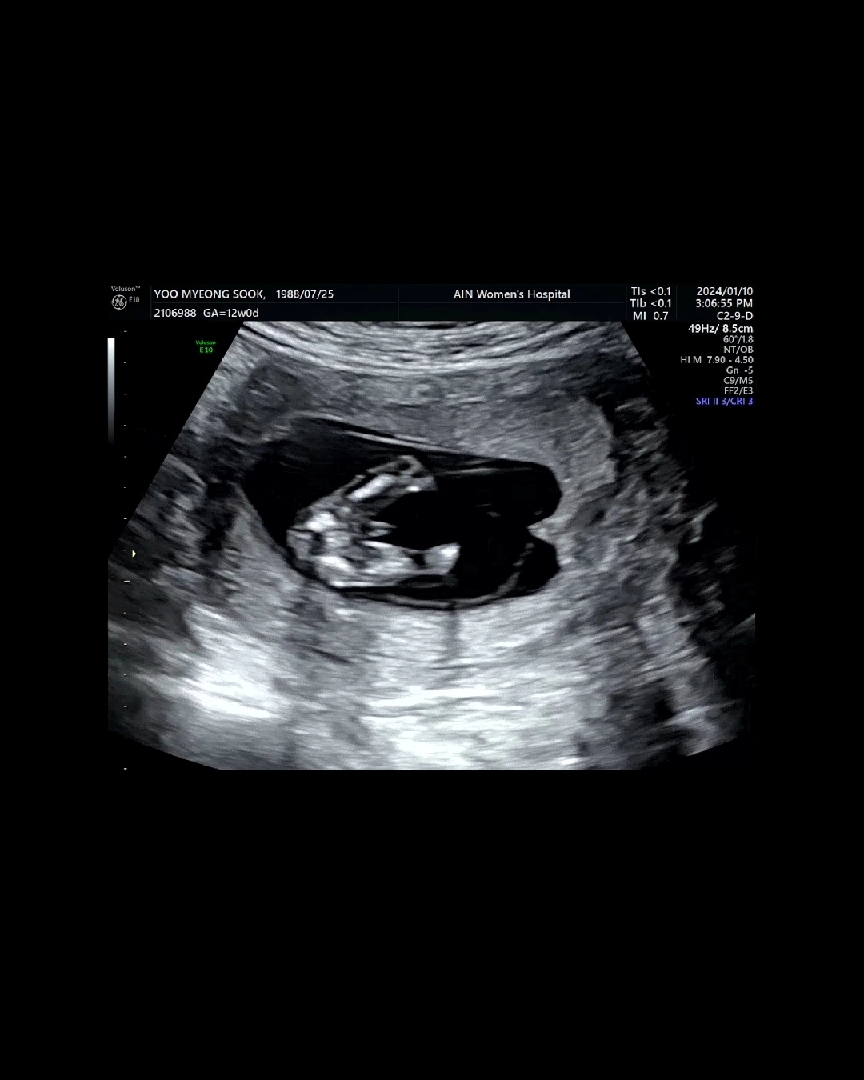

딱 봐도 아들이죠???^^

쌤이 존재감이 있어보인다고 하셨는데..ㅋㅋ 진짜 그런것 같죠?ㅋㅋㅋㅋㅋ 아들이죠?ㅋㅋㅋ

딱 12주때 본거예요ㅋㅋ 입체촘파는 더 잘보여요ㅋㅋㅋㅋㅋㅋ 감사해용😍

ㅋㅋㅋㅋㅋㅋ저렇게 확실히 보일지 몰랏는데 성별 기대도 없이 갓다가..ㅋㅋㅋ 너무 잘보여서 놀랬어요ㅡㅋㅋ

반전이 있을까요?ㅋㅋㅋㅋ감사해용ㅋㅋ 다리도 통통. 고추도 통통 한것같아요 ㅋㅋ